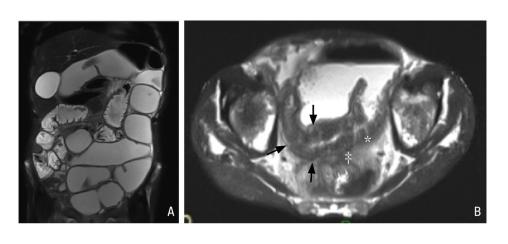

Sténose au cours d’une maladie de Crohn iléale chez un patient de 51 ans.

Dilatation d’amont visible en séquences pondérées T2 en coupe coronale (A) ; sur la coupe B, la sténose avec un épaississement pariétal (flèches) s’accompagne d’ulcérations profondes (*) et d’une fistulisation au rectosigmoïde en arrière (‡).